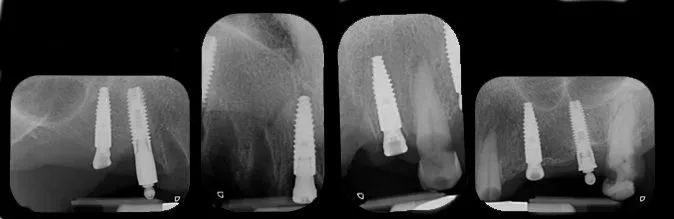

The postoperative x-ray images confirmed the precision of the implant placements in sites 16, 11, 22 and 25 (Fig. 40).

Fig. 40

Prosthetic procedure

The patient returned for a follow-up three months after the placement and healing of the upper and lower implants. Examination showed healthy surrounding tissues, osseointegrated implants, and no signs of inflammation or complications. X-ray images taken at this stage confirm the quality of osseointegration in the upper and lower jaws (Fig. 50).

Fig. 50.